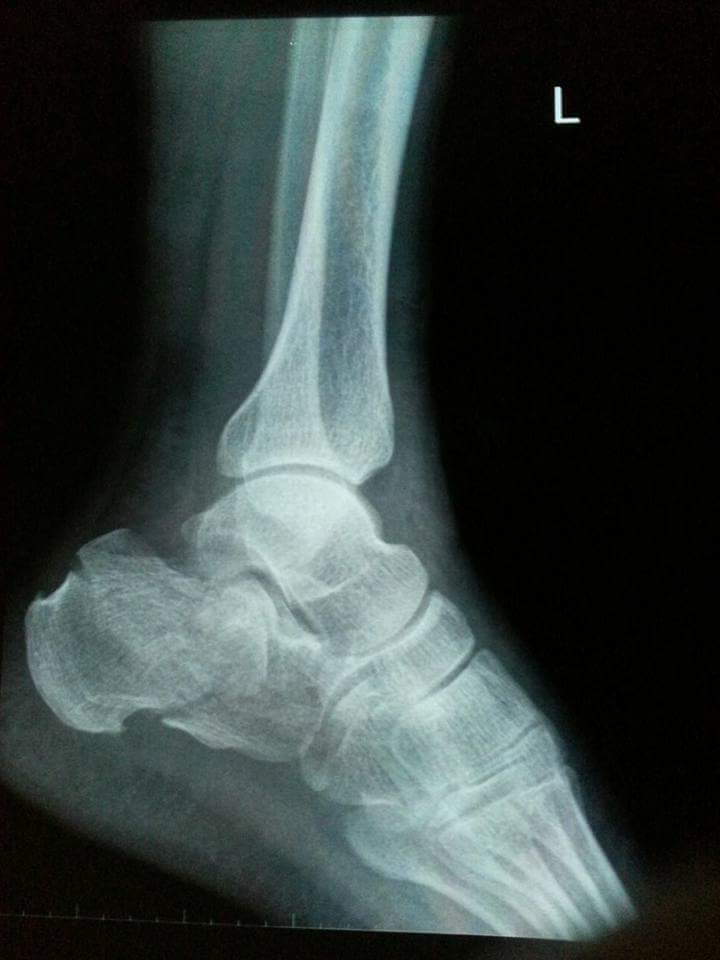

My father fell off from height 3 weeks back and got his left calcaneus fractured. We saw a doctor the same day who applied plaster cast on his foot and adviced icing and foot elevation Later, we saw another doctor who adviced cast removal immediately and starting physiotherapy and exercises. The latter also said that cast should not have been applied in this particular case. Also, the cast application on the same day of fracture could cause ischemia due to impending swelling.

this fracture need surgery for better functional outcome

This needs surgery